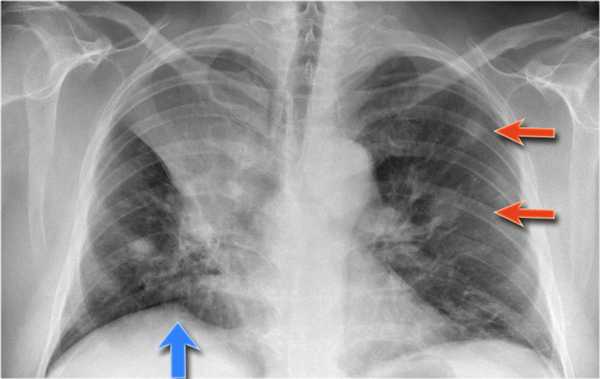

Также очень частым проявлением ателектаза является подъем диафрагмы, что хорошо визуализируется на ниже представленной рентгенограмме (указано синий стрелкой).

У данного пациента карцинома легкого с билатеральным метастазированием в легкие (указано красными стрелкам).